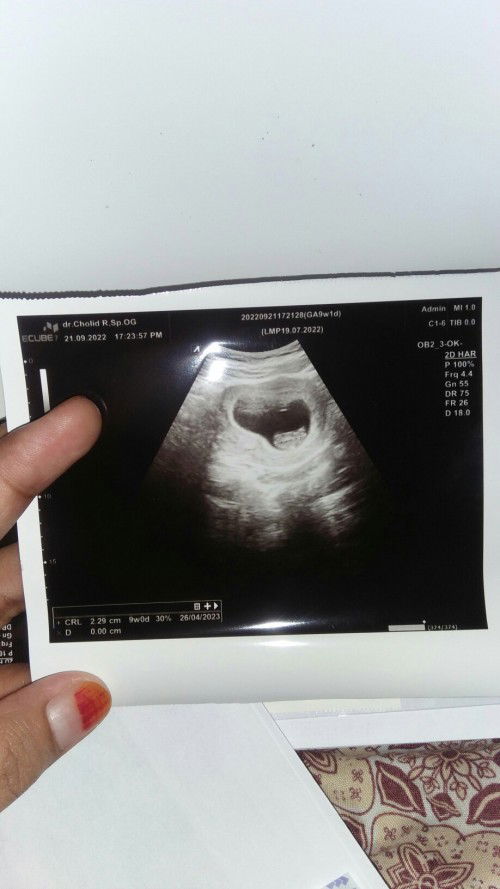

Awal usg usia 5w masih kantong dan belum bisa dideteksi ukurannya karna masih kuuecil.. Disuruh kontrol 1bulan kemudian Dan hari ini tepat 1bulan waktunya kontrol Alhamdulillah... Janin udah kelihatan ukuran normal.. Kmrin selalu overthinking, takut, setelah liat hasilnya jadi plong.. Minta doa nya bunda bunda.. Semoga janin saya sehat, normal, sempurna, berkembang bagus sampai lahiran normal gangsar aamiin... Penantian 2thn #semangatpejuang2garis